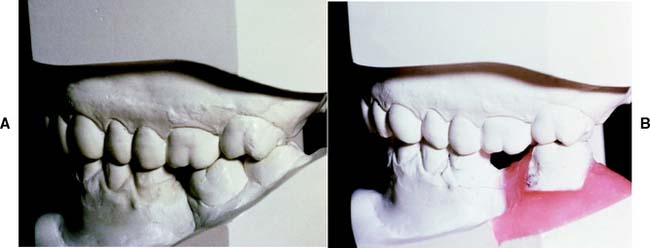

The need for orthodontic treatment is determined through a careful analysis of articulated diagnostic casts, whose usefulness can be enhanced with a dental surveyor (Fig. 6-22). One helpful procedure86 is to section a duplicate cast (Fig. 6-23) and reassemble it according to the proposed orthodontic modifications. This facilitates assessing the validity of any minor tooth movement (e.g., closing diastemas, uprighting molars, aligning tilted teeth) and is especially valuable when explaining the treatment proposal to the patient. Diagnostic preparations and waxing procedures made on these altered casts often clearly illustrate the benefits of minor tooth movement. Many dentists are now using computer imaging technology to optimize esthetic treatment planning and improve patient communication87-90 (Fig. 6-24).

Fig. 6-22 A and B, Use of diagnostic preparations and a dental surveyor in assessing the need for orthodontic treatment before fixed prosthodontics.

Fig. 6-23 A and B, Diagnostic cast sectioning for determination of desired orthodontic tooth movement.